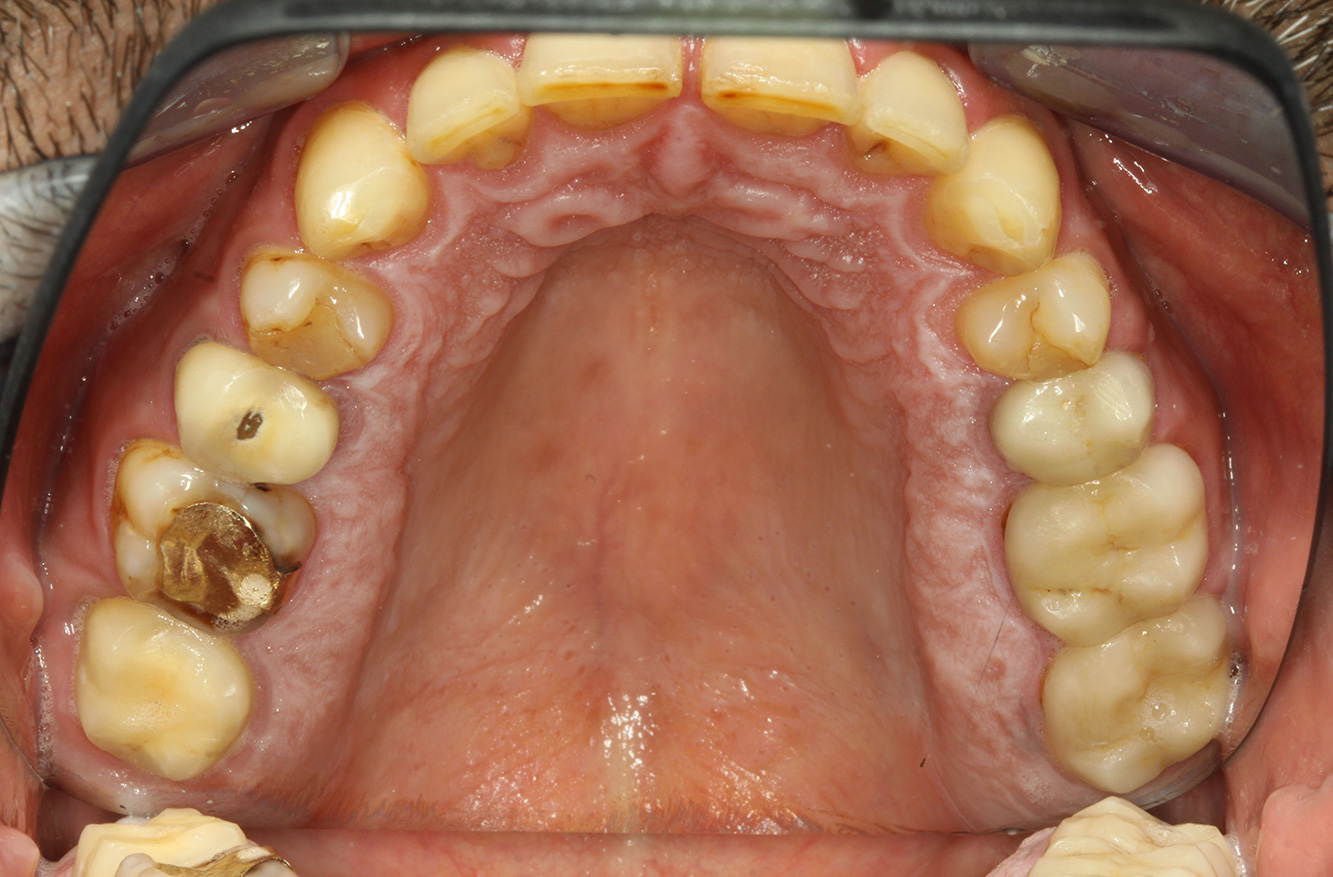

The patient is 39 years old and has previously undergone aortic valve replacement due to valve failure and endocarditis. ASS 100 is taken regularly as an anticoagulant. In terms of lifestyle, the patient’s diet is classified as caries-promoting due to the regular consumption of sugary foods and the fact that six to seven meals are consumed daily. The patient’s oral health indicates a moderate risk of caries, with active lesions. The risk of periodontitis is low, but gingivitis is present. The following recommendations are made for prophylactic treatment.

No specific instrument recommendations can be determined for the prophylaxis session. Targeted application of air and rotary polishing can be used to gently reduce plaque and stains on the restoration edges, and to reduce recolonization niches for cariogenic bacteria (19).

Fluoridation is recommended to further support the prevention of caries, and especially to prevent new formation around the restoration edges, and to seal the root surfaces. Both of these measures can reduce the teeth’s sensitivity to temperature.

Due to the active caries lesions and the associated risk of progression, a shortened recall interval of three to four months is recommended.